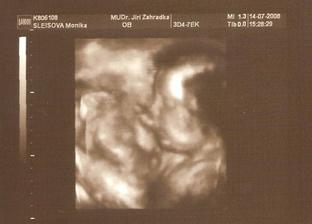

14.7. 3D utz - nádherný zážitek. i když mrňousek moc nespolupracoval a pořád se schovával. Navíc je v plodovce asi dost šupinek mázku, tak jsou fotečky neostré. I tak to bylo krásný. A podle statistik máme termín 12.10. 😲